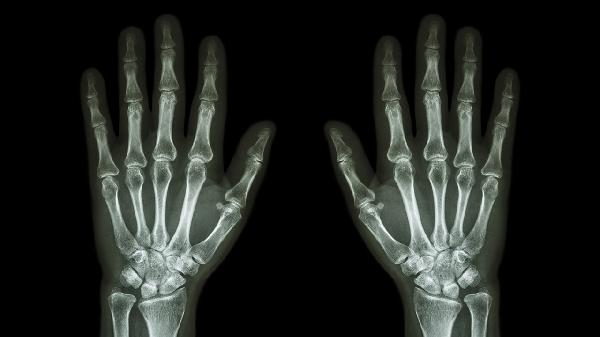

关节软骨退行性变会引发中指关节晨僵、活动时有摩擦感。X线可见关节间隙狭窄和骨赘形成。可遵医嘱使用硫酸氨基葡萄糖胶囊、双醋瑞因胶囊等软骨保护剂,配合关节腔注射玻璃酸钠注射液。